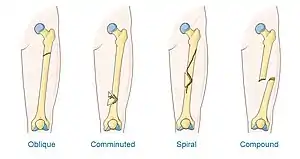

A Maisonneuve fracture may be a simple fracture or comminuted fracture:[12][19]

- A simple fracture, in the case of a Maisonneuve fracture, refers to the fibula being broken in one place without any damage being done to the surrounding tissues.

- A comminuted fracture is when the bone is broken in more than two places.

X-ray, CT, or MRI can be used to diagnose the extent of damage and determine whether it is a simple or comminution fracture.[12] During diagnosis, a supination-external rotation pattern of injury may also be concluded if there is an isolated fracture of the posterior tubercle of the tibia.[11]